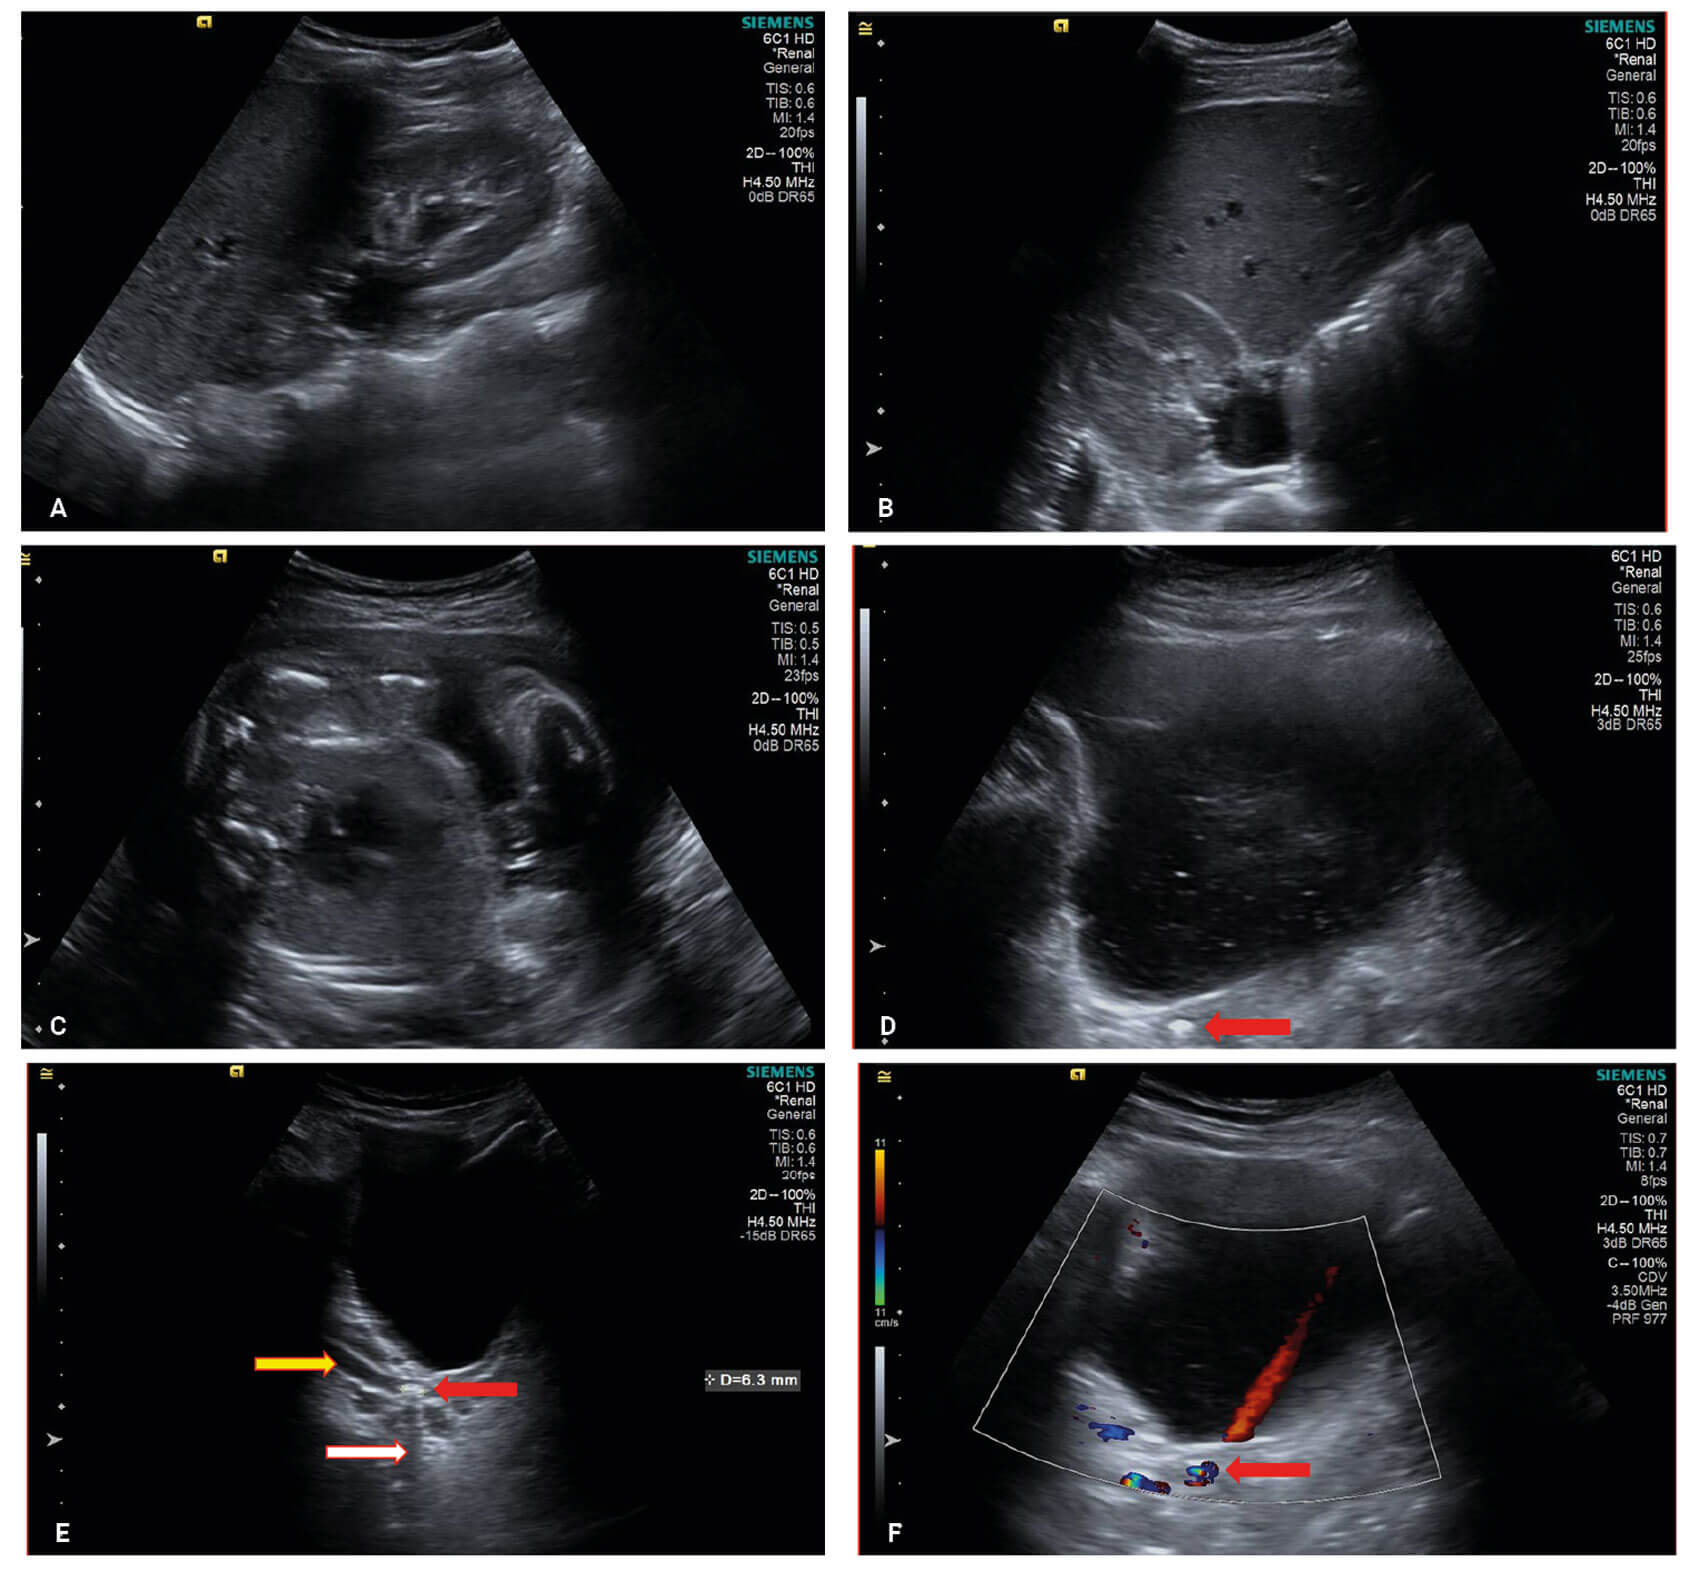

Kidney stones in pregnancy

Urolithiasis related complications are estimated to affect between 1:200 and 1:2000 pregnancies [1,2]. With around 825,000 conceptions in England and Wales in 2021 [3], this represents an uncommon but not rare occurrence. What is normally a straightforward pathway for a...